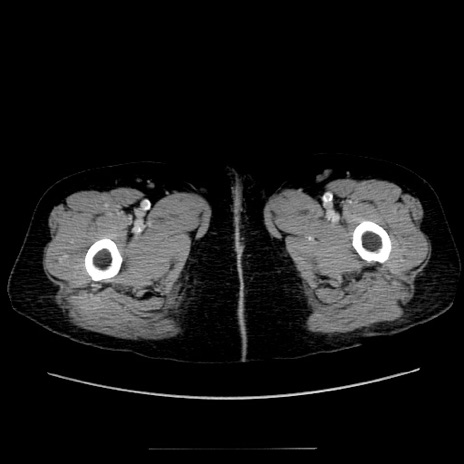

冠状断像

【症例】70歳代女性

【主訴】お腹が張る

【現病歴】1週間くらい前から腹部膨満の自覚あり。昨日夜から増悪したため、本日救急外来受診。

【身体所見】意識清明、BT 36.5℃、BP 165/106mmHg、HR 80bpm、SpO2 98%、腹部:膨満、軟、自発痛・圧痛なし、触診にて不快感あり、腸蠕動音:減弱

【データ】WBC 12600、CRP 1.04